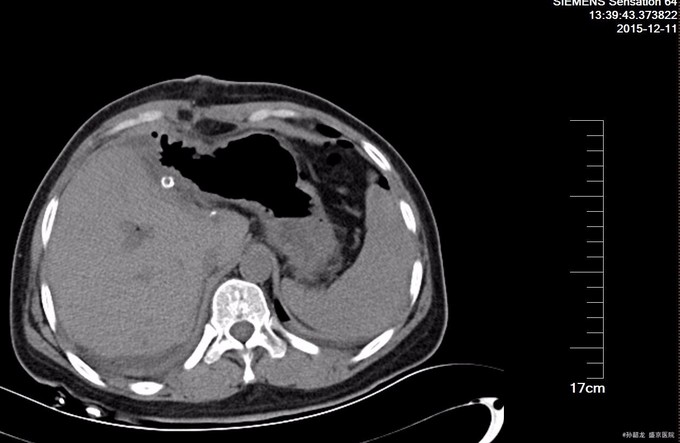

主诉:上腹部疼痛伴发热和恶心呕吐20余天。 病史:患者20天前进食后出现上腹部疼痛,伴有后背部疼痛和呕吐,呕吐后疼痛可缓解,之后出现寒战发热,就诊于抚顺某医院,行上腹部CT检查,提示:肝内外胆管多发结石,肝内外胆管扩张。脾大。胃窦壁略增厚。并予以保肝,抑酸,抗炎治疗,略好转,今患者为求进一步治疗来我院,门诊以“肝内外胆管结石“为诊断收入病房。病来饮食欠佳,睡眠正常,小便黄,大便干燥,一周便一次,近期体重减轻约10kg。

查体:全身皮肤及巩膜无黄染,腹软不胀,未见胃肠型及蠕动波,全腹平软,全腹无压痛及无反跳痛,无肌紧张,Murphy's征(-),肝区叩痛(-),双肾区叩击痛(-),移动性浊音(-),肠鸣音6次/分。 辅查: 肝功能化验,总胆红素及直接胆红素正常,转氨酶有升高。 MRCP提示胆囊增大,肝内外胆道内多发结石,伴胆道梗阻。 腹部BUS提示 1.肝外胆道梗阻, 2.肝门部胆管至胆总管内结石, 3.肝内胆管结石。

诊断: 肝内外胆管结石 治疗:全麻下手术探查:胆囊约10*3.0*3.0cm,壁厚约0.3cm,与周围组织粘连,胆总管扩张,直径3cm,内可触及结石,肝脏左叶萎缩,内及结石,术中诊断胆囊炎 ,胆总管结石,左肝萎缩,左肝内胆管结石,行胆囊切除,左半肝切除, 胆总管切开取石 ,T 管引流术。术后病理证实(左半)肝内胆管结石,伴慢性炎症,慢性胆囊炎。